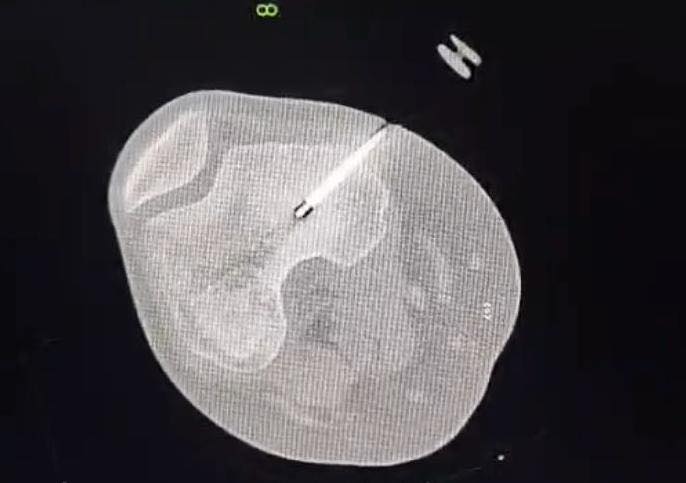

السوسنة - اجرى الكادر الطبي في مستشفى الأميرة بسمة عملية نوعية دقيقة لعلاج ورم عظمي حميد من نوع (Osteoid Osteoma) باستخدام تقنية الكي بالتردد الحراري (Radiofrequency Ablation) الموجهة بالأشعة المقطعية.

وتم إجراء هذا التدخل بنجاح من قبل الدكتور محمد نصر نزال والدكتور عثمان أبو قران أخصائيي الأشعة التداخلية وقسطرة الأوعية الدموية وبإشراف ومتابعة الدكتور عمر سميرات (أخصائي عظام الأطفال).

وبين الفريق الطبي أن خصوصية هذه الحالة تكمن في عمر المريضة (14 عاماً) حيث استقر الورم مباشرة على صفيحة النمو (Growth Plate) في عظم الفخذ البعيد. وتعتبر هذه المنطقة من الحساسية بمكان إذ ان أي خطأ قد يؤثر على النمو المستقبلي للعظم ما جعل استخدام تقنية الكي الحراري تحديا كبيرا يتطلب دقة فائقة لتجنب إلحاق أي ضرر حراري بالأنسجة المحيطة.

وبحسب بيان للمستشفى، تكللت العملية بالنجاح ، وتماثلت المريضة للشفاء واختفت آلامها الشديدة فور انتهاء الإجراء وهو ما يثبت فعالية العلاجات الحديثة "قليلة التداخل" في التعامل مع أعقد الحالات الطبية.